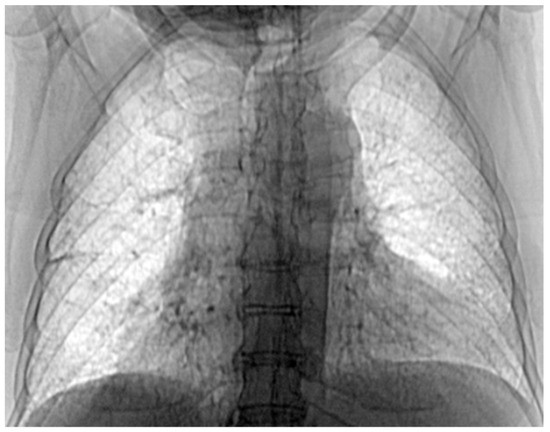

3.7. Results of Healthy Patients—A Final Comparison Using Control Data

In this subsection, we present and discuss the pulmonary CT scan of healthy lungs, which were not affected by the presence of SARS-CoV-2.

The chest radiograph of healthy lungs on which the fractal analysis was performed is shown in Figure 29a. Aside from the high-quality imaging provided by CT procedures (Figure 29a,b), the picture evaluation assured quantitative information regarding various structural features, such as the fractal dimension and lacunarity.

Figure 30 shows the 2D box-counting algorithm with the local fractal dimension calculation for the healthy-lung CT image. Figure 31 displays the 3D graphical representation of the voxels present in the CT lung image of healthy patient. Table 7 presents the calculated values for the fractal dimension and the lacunarity of the CT image evaluations for the healthy patient.

Figure 29. (a) Healthy lung image, (b) binary version, (c) mask for the left lung, (d) mask for the right lung.